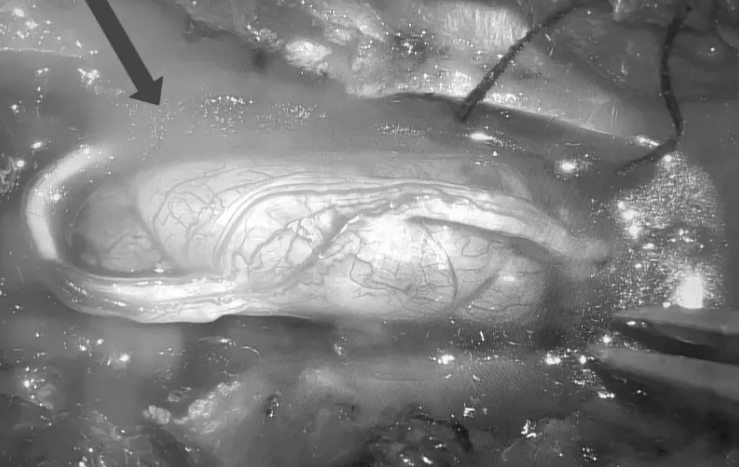

Hình ảnh chụp MRI khối u tủy trong ống sống ngực của bệnh nhân. Ảnh: Bệnh viện cung cấp

TS Nguyễn Khắc Hiếu,khoa Ngoại Thần kinh,cùng êkíp vi phẫu thành công loại bỏ hoàn toàn khối u tủy kích thước 1,5 x 2 cm trong ống sống ngực bệnh nhân. Hậu phẫu,hai chân bệnh nhân phục hồi vận động,lấy lại cảm giác,năm ngày sau có thể đi lại nhẹ nhàng.

Bác sĩ Hiếu đánh giá đây là một ca khó,bệnh diễn biến cấp tính và dễ nhầm với bệnh lý khác. Khối u không lớn nhưng nằm ở vùng tủy ngực là nơi ống sống chật hẹp,chỉ cần một tác động nhỏ khi phẫu thuật cũng có thể gây tổn thương tủy.